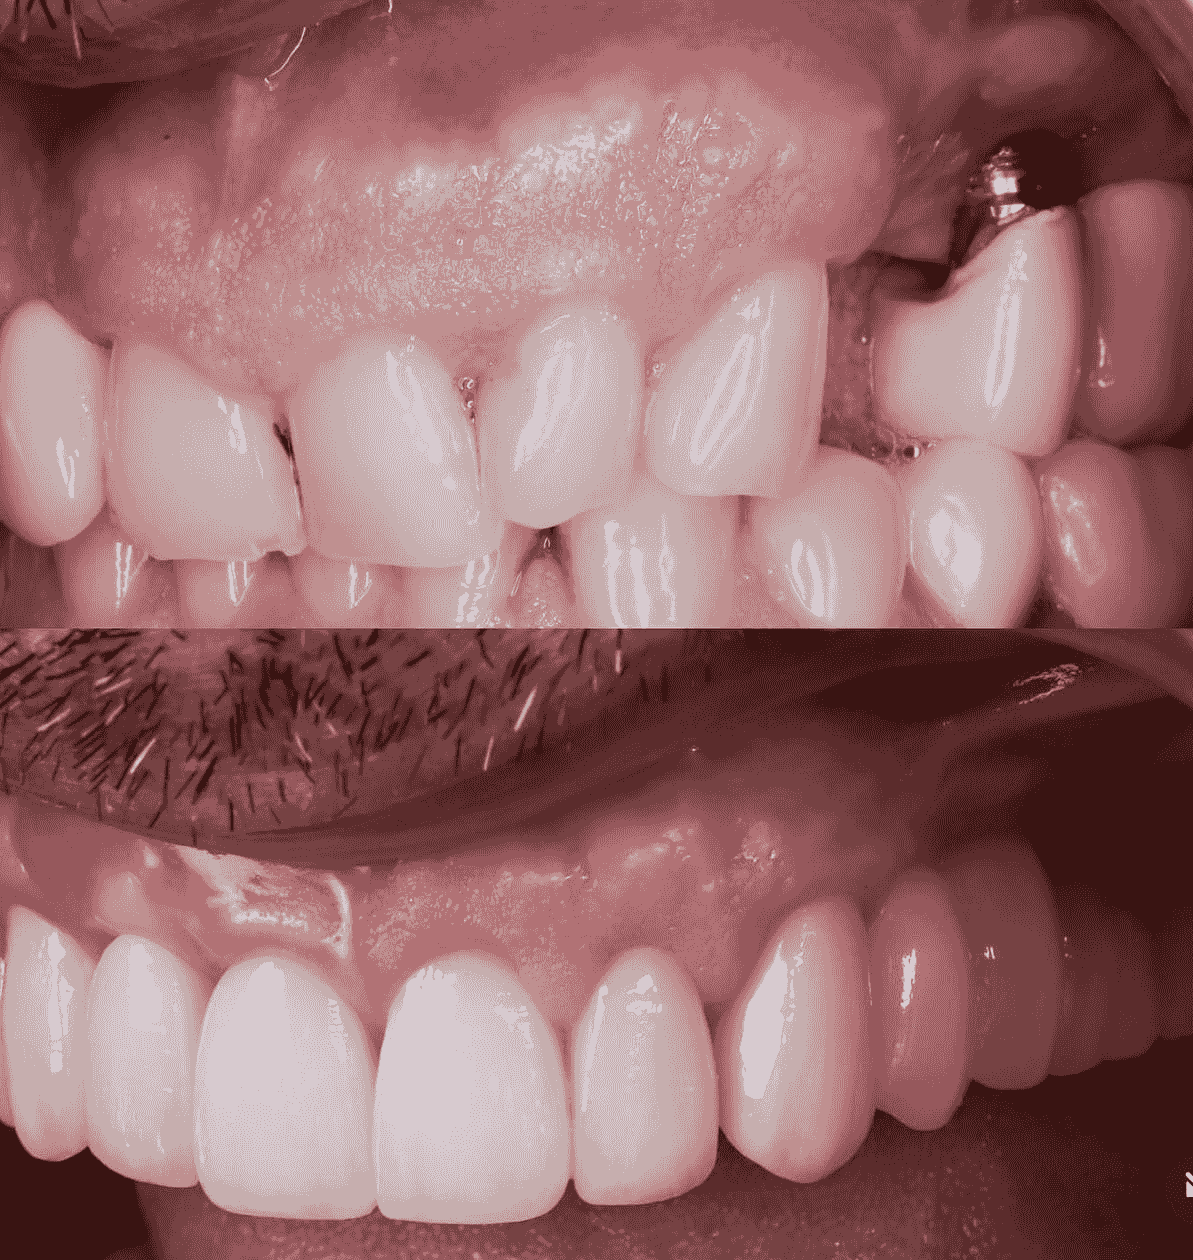

Resultados visibles

Muchos de nuestros pacientes comparten su satisfacción por los resultados obtenidos, mejorando su salud bucal y su autoestima.